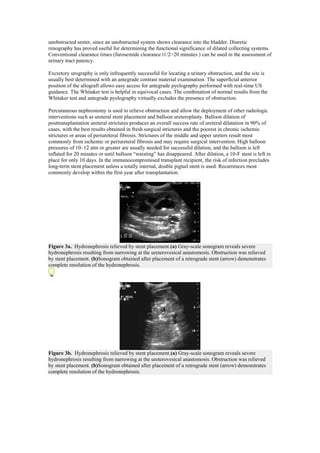

Figure 3a. Hydronephrosis relieved by stent placement.(a) Gray-scale sonogram reveals severe

hydronephrosis resulting from narrowing at the ureterovesical anastomosis. Obstruction was relieved

by stent placement. (b)Sonogram obtained after placement of a retrograde stent (arrow) demonstrates

complete resolution of the hydronephrosis.

Percutaneous nephrostomy is used to relieve obstruction and allow the deployment of other radiologic

interventions such as ureteral stent placement and balloon ureteroplasty. Balloon dilation of

posttransplantation ureteral strictures produces an overall success rate of ureteral dilatation in 90% of

cases, with the best results obtained in fresh surgical strictures and the poorest in chronic ischemic

strictures or areas of periureteral fibrosis. Strictures of the middle and upper ureters result most

commonly from ischemic or periureteral fibrosis and may require surgical intervention. High balloon

pressures of 10–12 atm or greater are usually needed for successful dilation, and the balloon is left

inflated for 20 minutes or until balloon ―waisting‖ has disappeared. After dilation, a 10-F stent is left in

place for only 10 days. In the immunocompromised transplant recipient, the risk of infection precludes

long-term stent placement unless a totally internal, double pigtail stent is used. Recurrences most

commonly develop within the first year after transplantation.